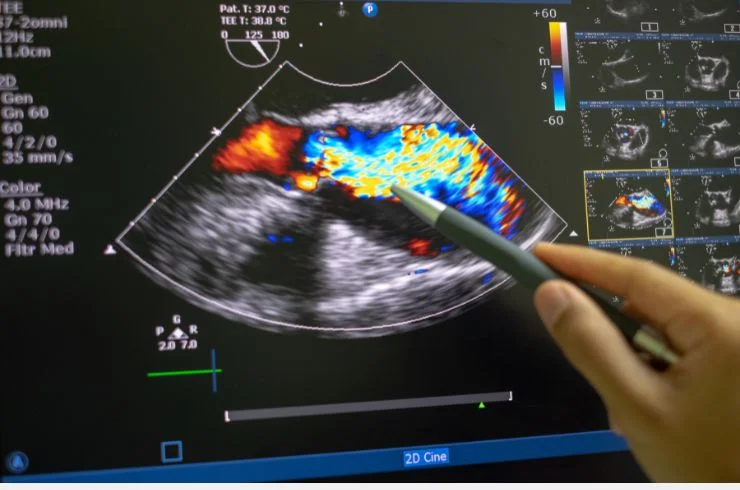

Advanced imaging to assess blood flow in arteries and veins, aiding in the diagnosis of vascular conditions with precision and reliability.